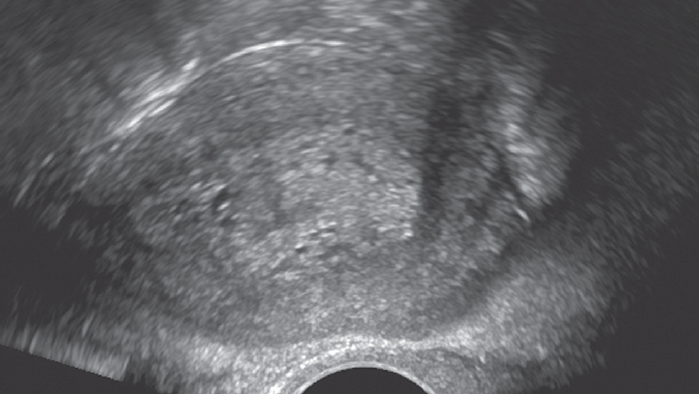

При трансвагинальном УЗИ эндометриальная карцинома может иметь вид полипа, гиперплазии эндометрия или неоднородного образования в просвете неравномерно расширенной полости матки (рис. 4). В случае инвазии в миометрий в дополнение к увеличению толщины эндометрия его граница становится нечеткой [39, 40].

Рис. 4. Постменопауза 5 лет. Кровянистые выделения из половых путей. Прием тамоксифена 5 лет. Увеличение толщины эндометрия до 39 мм. Инвазия в миометрий. Морфологически — рак эндометрия

Fig. 4. 5 years postmenopausal, after 5 years of Tamoxifen therapy. Bleeding from the genital tract. Endometrial thickness is increased to 39 mm. Invasion of the myometrium. Endometrial cancer (morphology study)